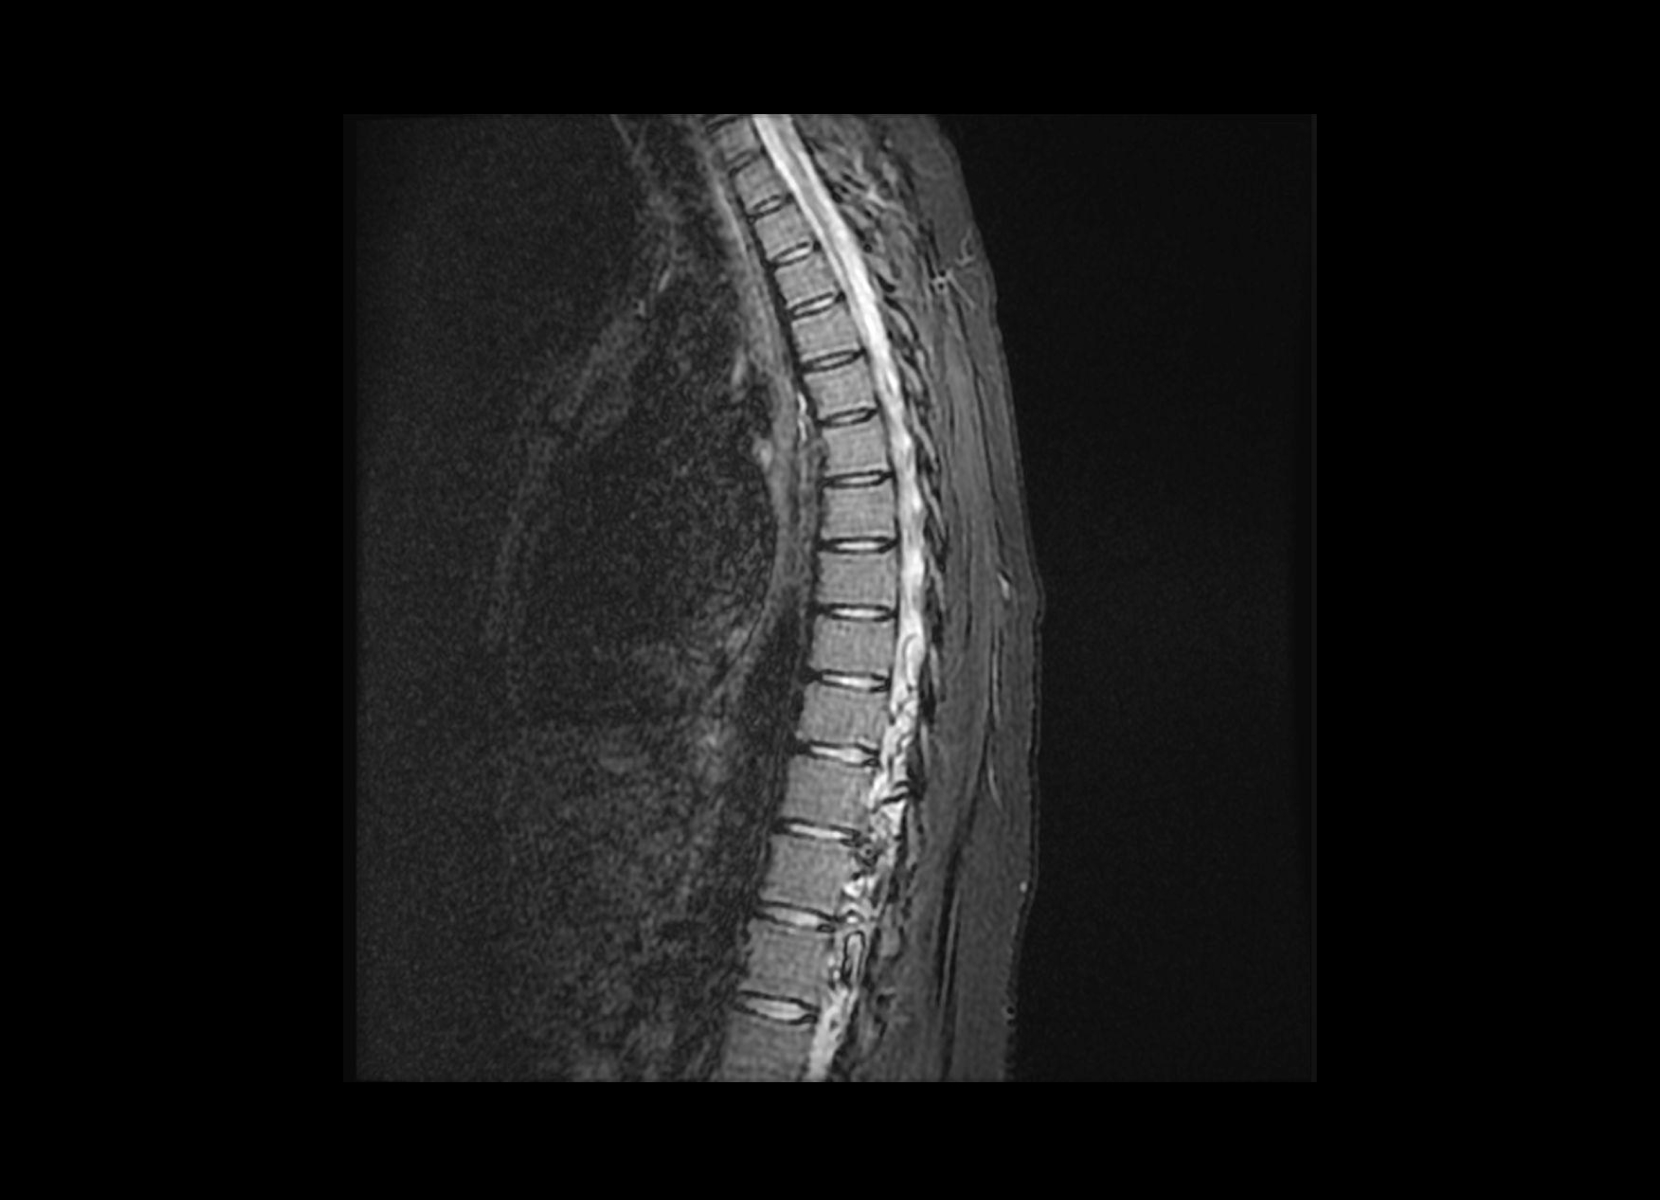

Conventional

STIR

SubtleSYNTH™

(Synthesized STIR)™

Trauma

GE 1.5T

C-spine